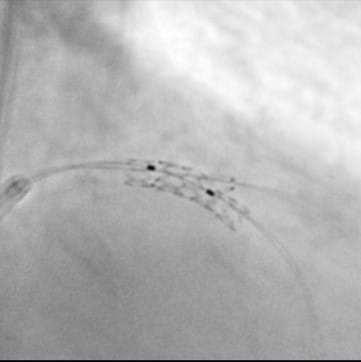

また、従来の装置では抽出困難であった冠動脈ステントや大動脈ステントの形状も明瞭に抽出できる高い画像解像度があり、頭頸部、心臓、腹部、四肢領域の画像下治療に大きな威力を発揮します。さらに最新の画像処理機能によって、従来の被ばく線量に比べ最大80%の被ばく低減を実現させています。

脳動脈瘤やクモ膜下出血に対して金属コイルを詰め、血管を塞栓する脳動脈瘤塞栓術、脳梗塞に対して血栓を溶かして血流を再開通させる血栓溶解術、頸部動脈狭窄に対してステントを留置し血管を拡張する頸部動脈ステント留置術などを行っています。

狭心症や急性心筋梗塞に対して冠動脈にステントを留置する冠動脈ステント留置術やFFR、iFRといった冠動脈の血行動態的有意狭窄を評価するカテーテル検査も行っています。心房細動など不整脈の治療では、心臓内部の心筋を焼灼して治療するカテーテルアブレーションや冷却して心筋を凍結させて治療する冷却アブレーション(Cryo-ABL)などを行っています。